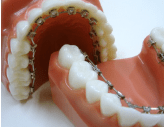

1.唇側からの矯正治療(ブラケット装置)

特徴は、ほかの矯正治療に比べ、費用を安く抑えることができます。

- 通院間隔は、1ヶ月に1度程度。

- 見た目は、目立ちます。

- 食事は、制限があります。

- 歯みがきは、手間がかかります。

2.装置が目立たない舌側矯正

特徴は、目立ちにくい歯の裏側に装着できることです。

- 費用は、歯の表面に装着するブラケット装置に比べ、高くなります。

- 歯の裏側に装着しているので、歯の表面に装着しているより歯みがきが難しくなります。